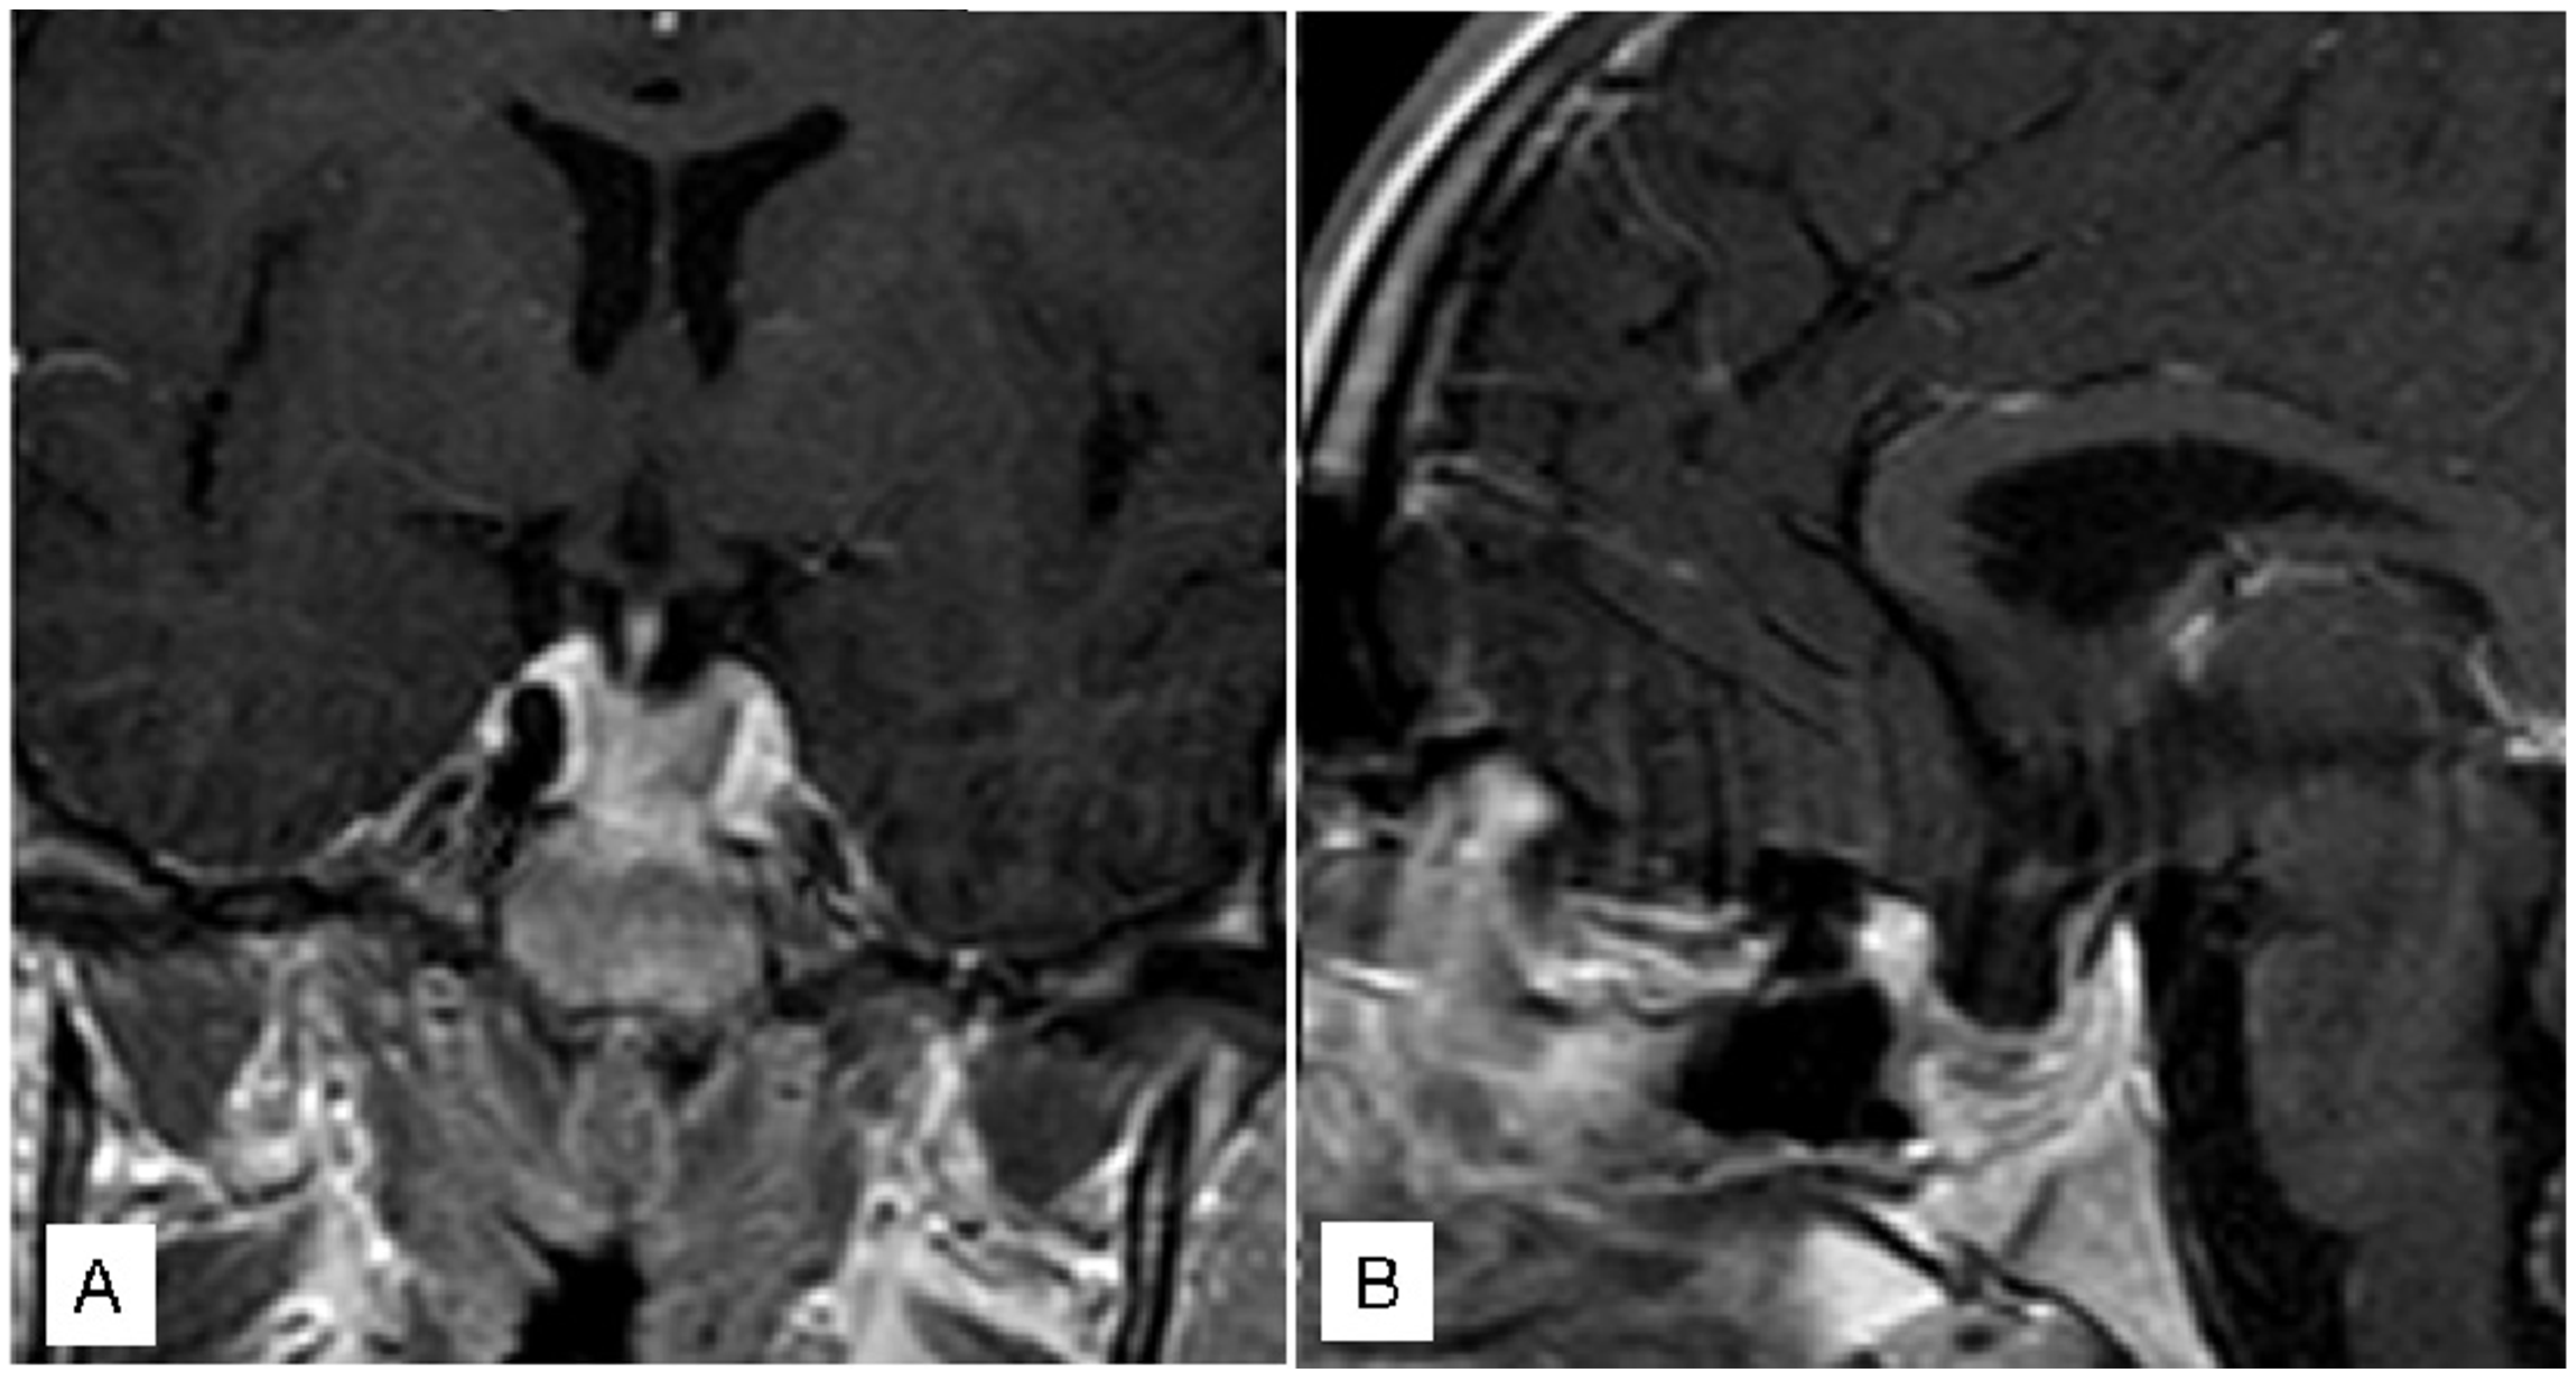

3.1.3. Case 3